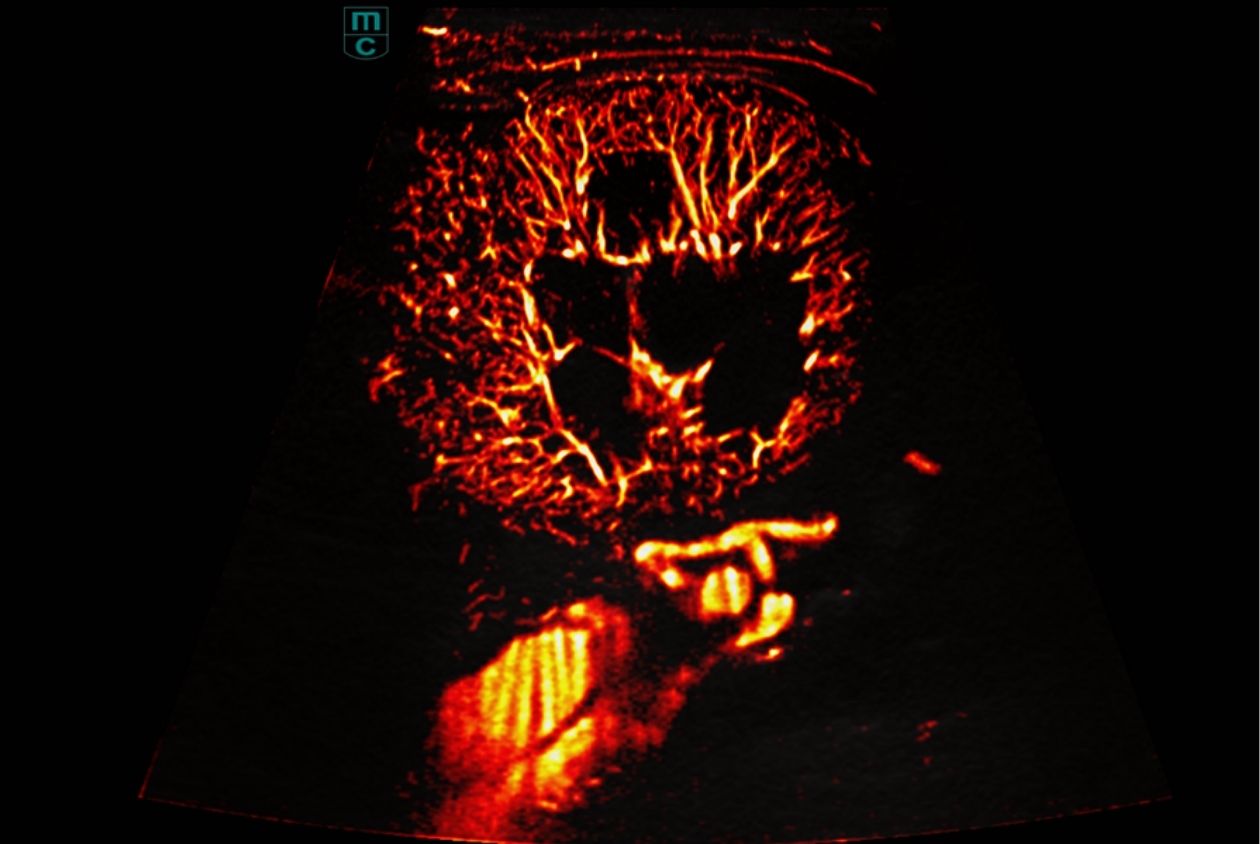

A closer look at just a few of our transducers: